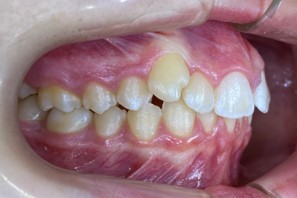

Chief complaint: We present the case of a 12-year-old female patient who came for an orthodontic evaluation, motivated by a family history of treatment. Clinical and radiographic analysis revealed a skeletal Class II malocclusion with molar and canine relationships also in Class II, moderate crowding in both arches, a deviation of the dental midline, and ectopic eruption of tooth 13. No functional issues with breathing or swallowing were observed, and oral health was generally good. A slight mandibular retrusion was noted in the soft tissue profile. A treatment plan was proposed using the Angel Aligner Pro system, aiming to correct dental misalignments and improve facial harmony through a minimally invasive, growth-adapted approach.

Clinical examination and diagnosis

- Woman ; 12/3 years

- Skeletal Class II

- Molar and canine Class II

- Upper and lower dentoalveolar compression

- Increased overjet and overbite

- Upper midline deviated 0,5 mm to the right

- Moderate upper and lower crowding